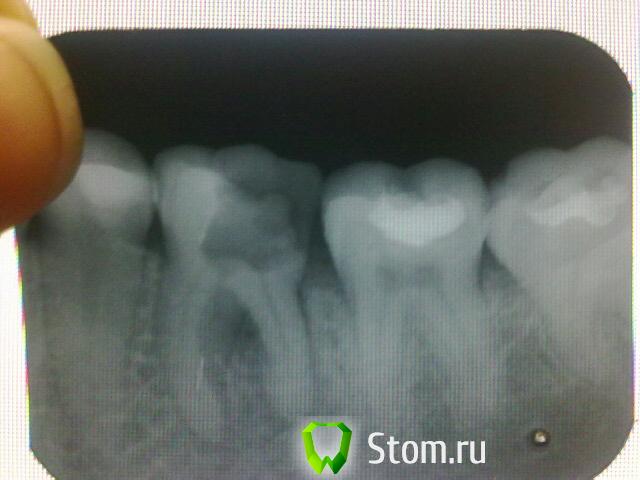

Bendertm Опубликовано 16 января, 2012 Поделиться Опубликовано 16 января, 2012 Добрый день!!! дней семь назад из-за сильной боли мне вскрыли зуб ранее депульпированный и запломбированный. после чего у меня распухла щека, по совету врача я полоскала содой и солью опухлость спала, но не до конца и недавно сделав снимок сказали , что его нужно удалять. У меня вопрос, можно ли его хоть как-нибудь сохранить. Не хочется терять зубик((((. Очень жду ответа. Спасибо Ссылка на комментарий

shishok Опубликовано 16 января, 2012 Поделиться Опубликовано 16 января, 2012 Боюсь,что доктора правы-воспаление между корней(скорее всего на дне кариозной полости имеется отверстие) .Прогноз неблагоприятный Ссылка на комментарий

DmitrySH Опубликовано 17 января, 2012 Поделиться Опубликовано 17 января, 2012 Я бы по данному снимку не брался столь категорично судить. Ссылка на комментарий

DmitrySH Опубликовано 17 января, 2012 Поделиться Опубликовано 17 января, 2012 Добрый день!!! дней семь назад из-за сильной боли мне вскрыли зуб ранее депульпированный и запломбированный. после чего у меня распухла щека, по совету врача я полоскала содой и солью опухлость спала, но не до конца и недавно сделав снимок сказали , что его нужно удалять. У меня вопрос, можно ли его хоть как-нибудь сохранить. Не хочется терять зубик((((. Очень жду ответа. Спасибо По снимку всего не сказать. Только при осмотре можно понимать на что расчитывать. Да, зуб проблема. Если хотите надежности рекомендую удаление и последующая имплантация. А вообще такое лечится 50/50 Ссылка на комментарий